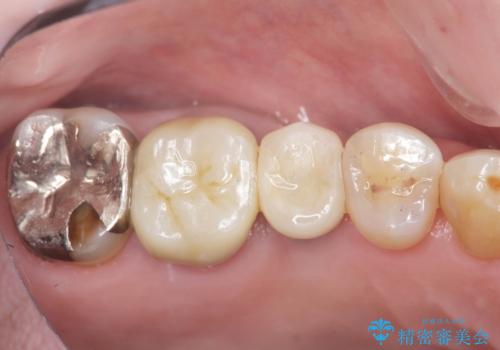

失った奥歯のインプラント治療

- 44万円(インプラント・チタンカスタムアバットメント・ジルコニアクラウン・仮歯)費用は治療当時の料金となります

「失った1本の歯の機能回復を行うだけでもずいぶん咬めるようになった。」、と咬合機能の回復を実感していただくことができました。